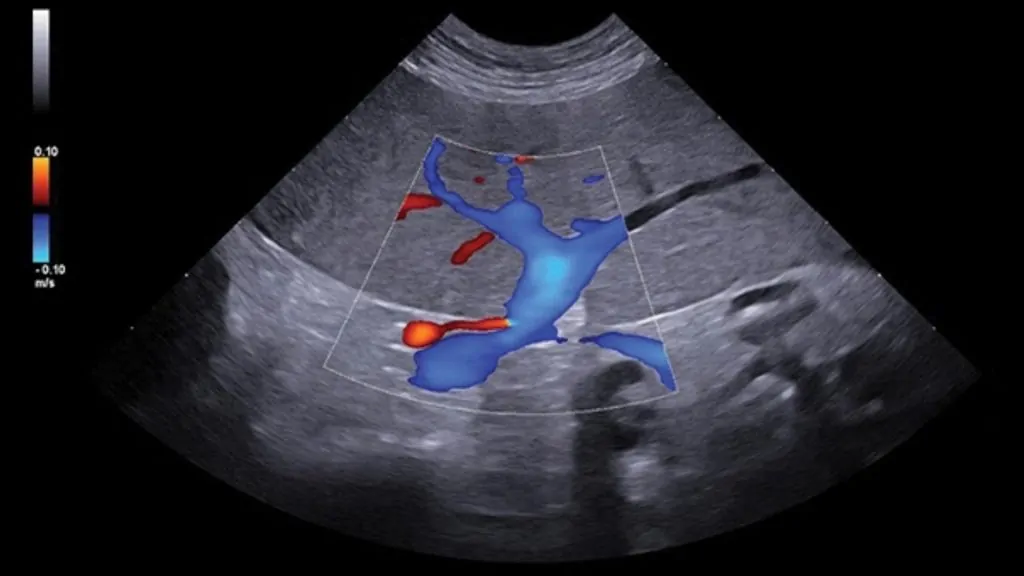

• Karın boşluğunda sıvı birikimi (efüzyon), gaz veya kitle varlığı

• Büyük damarlarda trombüs/emboli şüphesi gibi vasküler değerlendirmeler

• Gerekli görülen durumlarda Doppler USG ile kan akımı analizi yapılabilir.